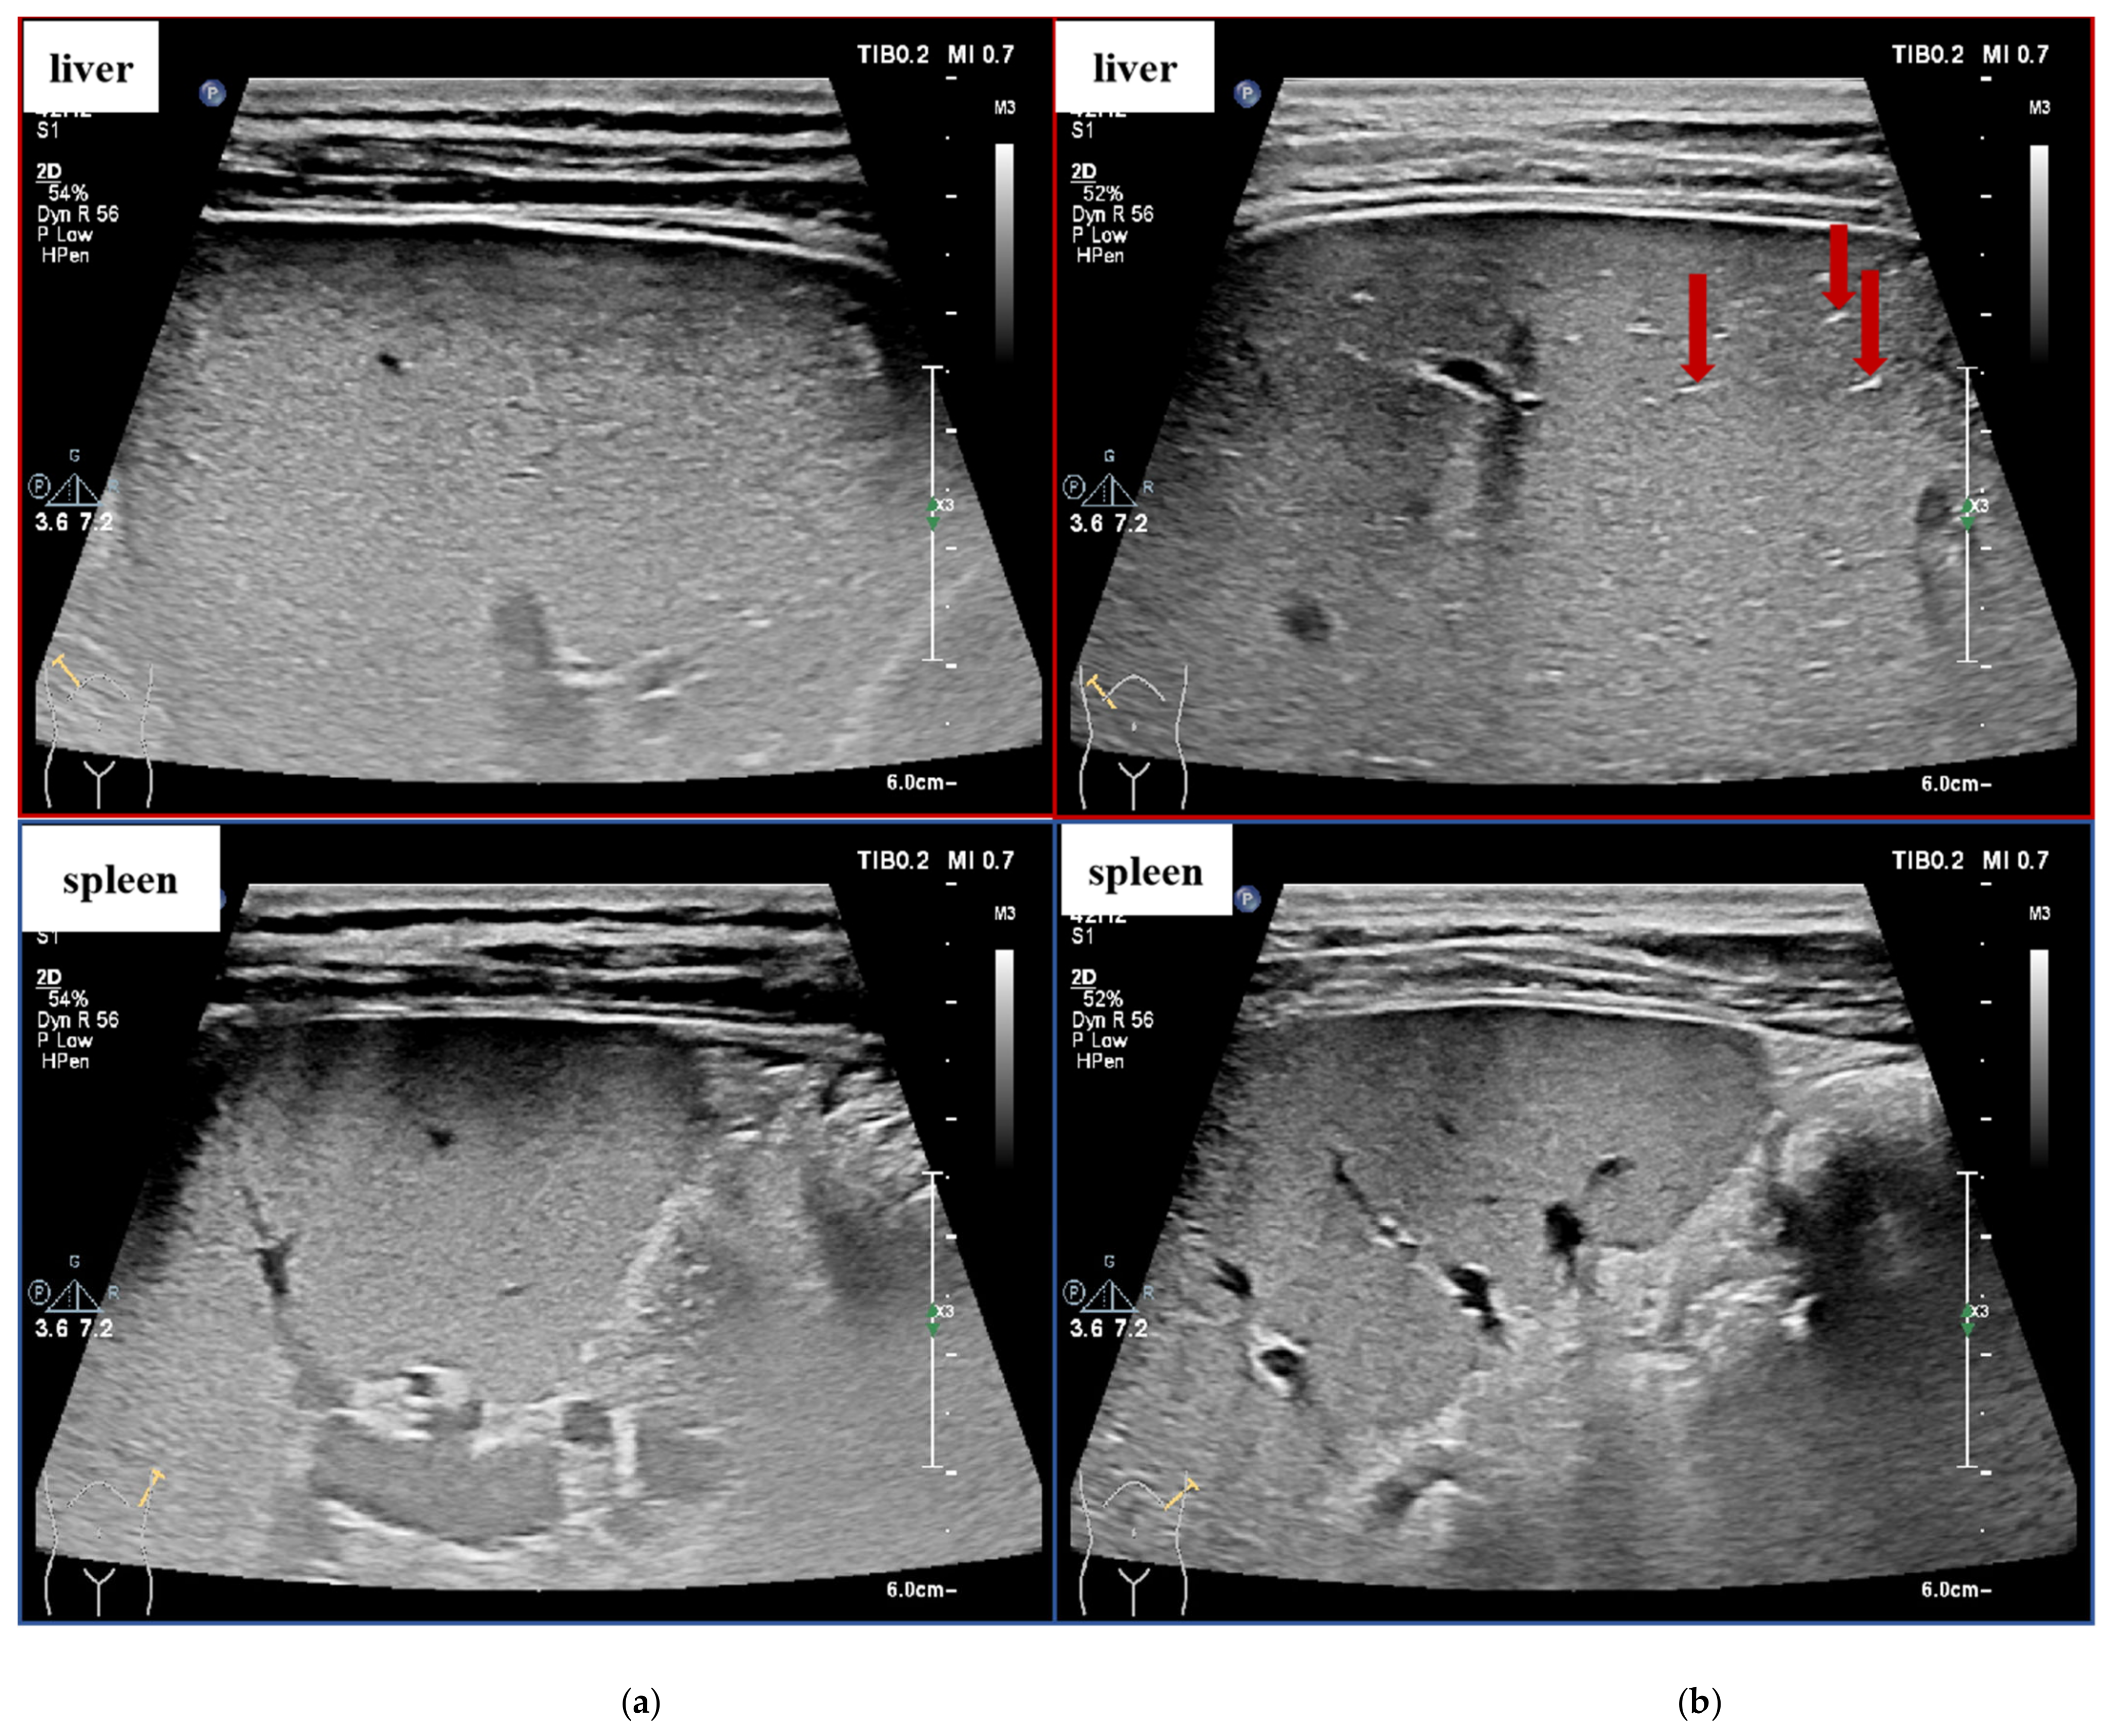

| Grade | Ultrasound Image Signs |

|---|---|

| 0 | Normal liver size, smooth liver capsule, homogeneous or slightly rough echo of liver parenchyma, clear vascular orientation, without splenomegaly. |

| 1 | Normal liver size, smooth liver capsule, rough echo of liver parenchyma, clear vascular orientation, without splenomegaly. |

| 2 | Moderate liver size, smooth liver capsule, significantly rough and enhanced echo of liver parenchyma, visible brightened linear structure shown as “strip pattern”, still clear vascular orientation, without splenomegaly. |

| 3 | Moderate or slightly smaller liver size, unsmooth liver capsule, significantly rough and enhanced echo of liver parenchyma with uneven distribution, with or without hyperplasia nodules, vague vascular terminals, with or without splenomegaly. |

| 4 | Smaller liver size, wavy liver capsule, significantly rough and unevenly enhanced echo of liver parenchyma, visible patchy enhancement, with or without nodules, variant vascular stenosis, with or without splenomegaly. |